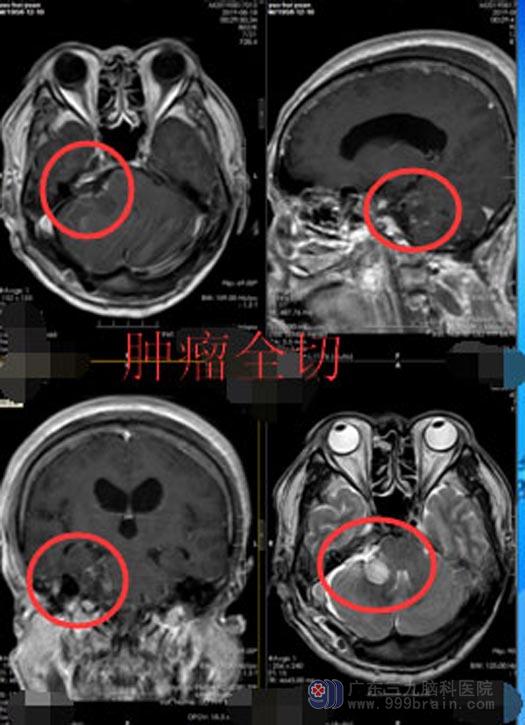

在充分的检查与准备后,鲁明副院长主刀为姚大爷行“右侧桥小脑角区听神经鞘瘤切除术”。术中可见肿瘤上至三叉神经,下达末组颅神经,与面、听神经、脑干明显粘黏,周边临近重要血管,手术的难度极大。通过手术导航,精准定位肿瘤位置,显微镜下细心地分块完整地切除了肿瘤,同时保护了重要的血管与神经,免其受损伤。历时7小时,手术顺利完成。

术后的姚大爷没有出现面瘫、嘴角歪斜、面部麻布等等后遗症,头痛头晕、听力下降的症状得到明显的改善。